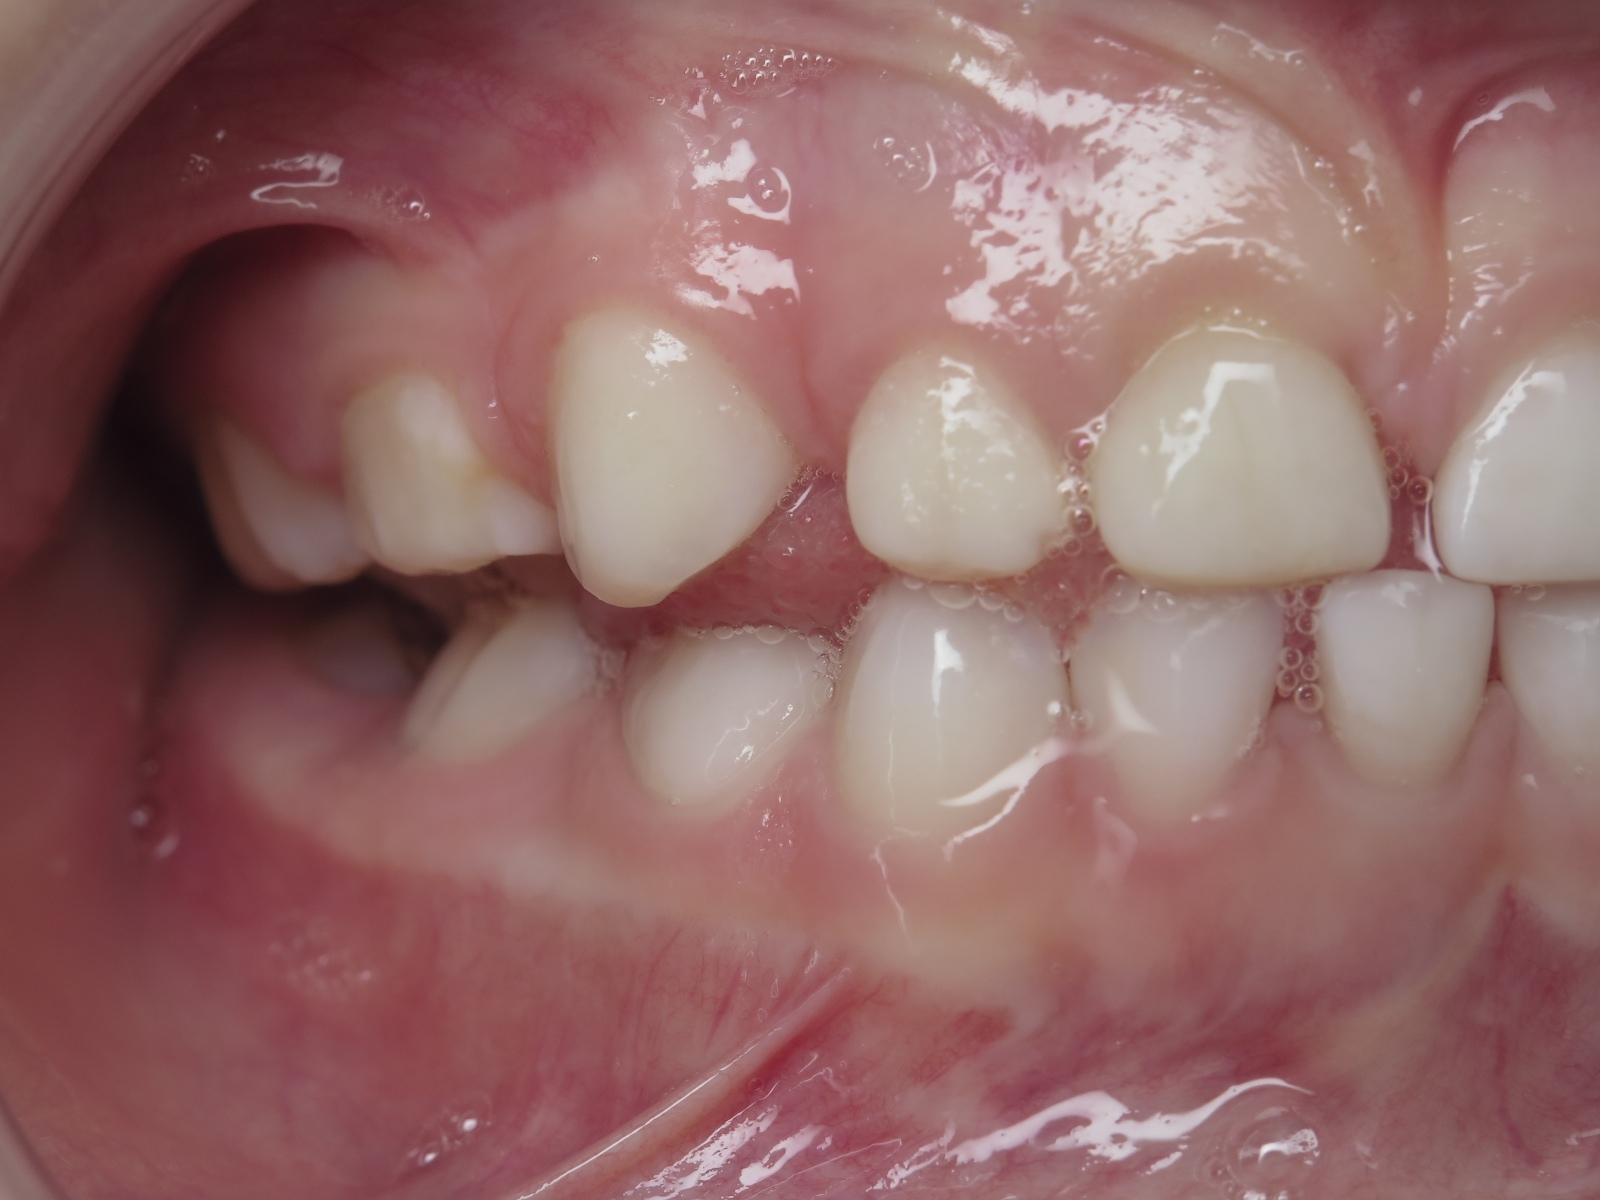

appareillage mobile pendant 13 mois

bilan début et en cours de traitement